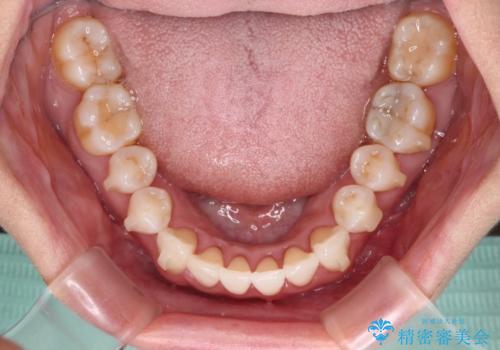

- 前歯の上下スペースによる食べにくさを気にして来院された患者様です。

インビザラインにより上下の前歯の隙間を閉じていくこととしました。

舌の突出癖があると上下前歯にスペースが開くため、矯正治療を機会に舌癖を改善するトレーニングを行ってもらい、矯正治療後の後戻りを防止するように指導しています。